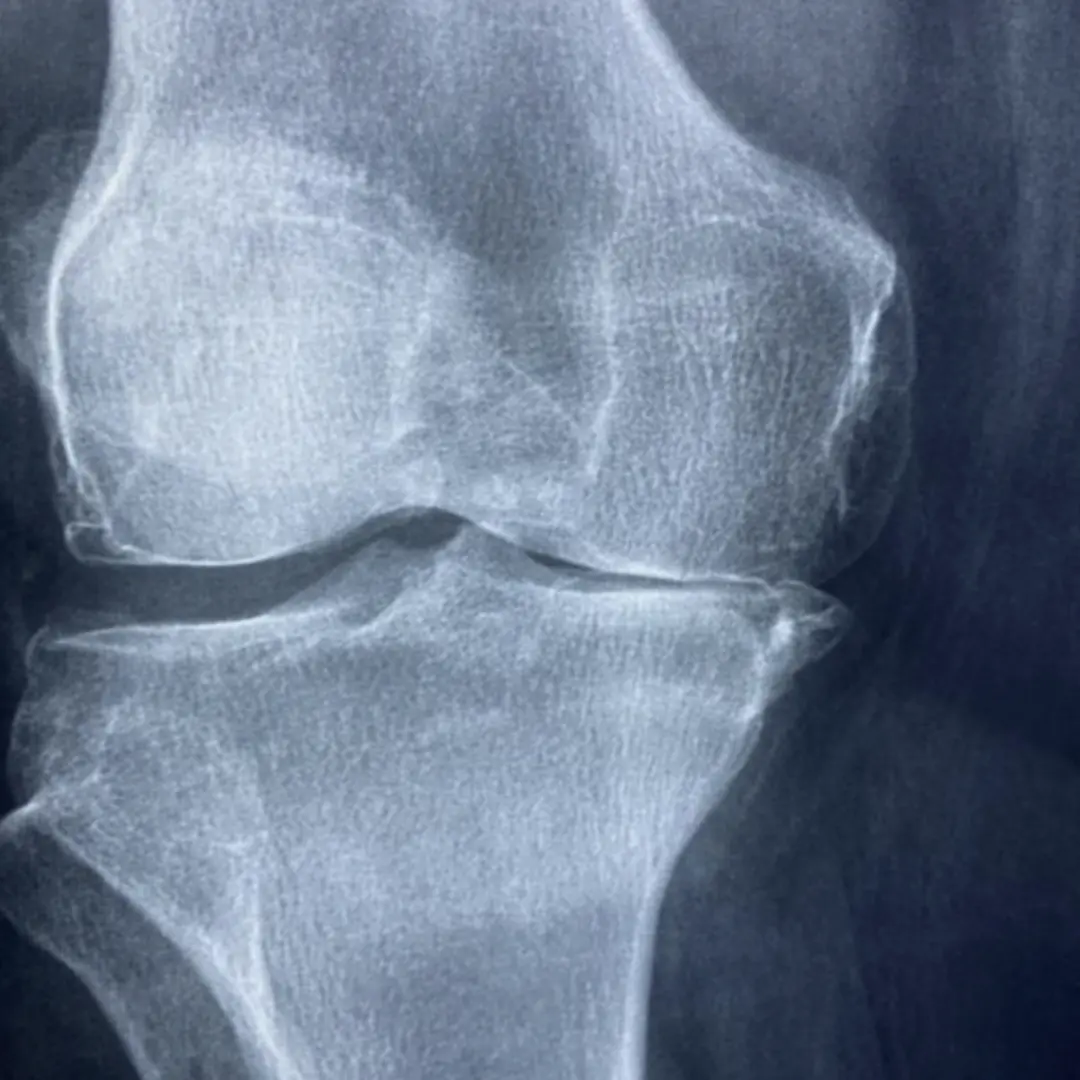

혹시 계단을 오르내릴 때 무릎이 시큰거리거나, 아침에 일어나면 손가락 마디가 뻣뻣하신가요? 그렇다면 관절 건강에 적신호가 켜졌을 가능성이 높아요. 지금부터 관절 건강 도움되는 관절영양제에 대해 자세히 알아보고 어떤 관절영양제가 나에게 맞는지 관절영양제 추천부터 선택 꿀팁까지 알아볼게요!